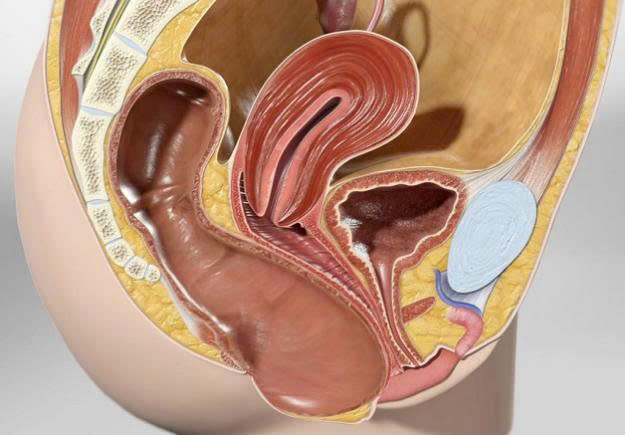

Biến chứng sa trực tràng do táo bón

Táo bón không chỉ là một vấn đề tiêu hóa thông thường mà còn ẩn giấu những nguy cơ đối với sức khỏe, điển hình là biến chứng sa trực tràng . Đây là hậu quả khi táo bón kéo dài mà người bệnh không được điều trị kịp thời. Vì vậy, ngoài những lưu ý quan trọng trong phòng chứa các bệnh lý nguy hiểm như ung thư, bạn cũng cần quan tâm đến sức khỏe hệ tiêu hóa của mình, đặc biệt nếu đang bị táo bón.

Sa trực tràng là gì và nguyên nhân làm bóng

tràng là phần cuối cùng của ruột già, đóng vai trò chứa phân trước khi được đào thải qua hậu môn. Khi bị táo bón, thường xuyên phải rặn mạnh để đẩy phân ra ngoài. Sự căng thẳng này tăng dần làm yếu các cơ giữ trực tràng ở vị trí bình thường, dẫn đến hiện tượng:

- Sa một phần hoặc toàn bộ trực tràng: có thể khiến một phần hoặc toàn bộ trực tràng bị sa xuống, trượt ra khỏi vị trí bình thường và cũng có thể ra cả ngoài cơ thể.

Triệu chứng của sa trực tràng

Biến chứng này thường bị với bệnh khác do chúng đều có biểu hiện ở vùng hậu môn . Tuy nhiên, sa trực tràng thường gây đau và nguy hiểm hơn. Các dấu hiệu nhận biết bao gồm:

- Ngứa sốt và kích thích xung quanh hậu môn: Do trực tràng sa gây đau hoặc viêm nhiễm.

- Đau vùng hậu môn: Cơn đau tăng lên khi đi vệ sinh hoặc vận động mạnh.

- Chảy máu tươi: Máu thường được trộn trong phân hoặc xuất hiện khi lau hậu môn.

- Rò rỉ phân tích: Khả năng kiểm soát kiểm soát phân suy giảm, gây rỉ phân ra ngoài.

Điều trị sa trực tràng

Việc điều trị phụ thuộc vào mức độ nguy hiểm của bệnh:

- Trường hợp nhẹ nhàng:

- Người bệnh được hướng dẫn thực hiện các bài tập tăng cường cơ trực tràng, suy nghĩ như bài tập Kegel , giúp cải thiện sức mạnh cơ bắp vùng chậu và giảm trạng thái sa trực tràng.

- Điều chỉnh chế độ ăn uống và thói quen sinh hoạt để giảm táo, hạn chế hoạt động xấu trực tràng.

- Trường hợp nặng:

- Nhưng nếu bị sa trực tràng nặng, cần thiết phải phẫu thuật khắc phục tình trạng